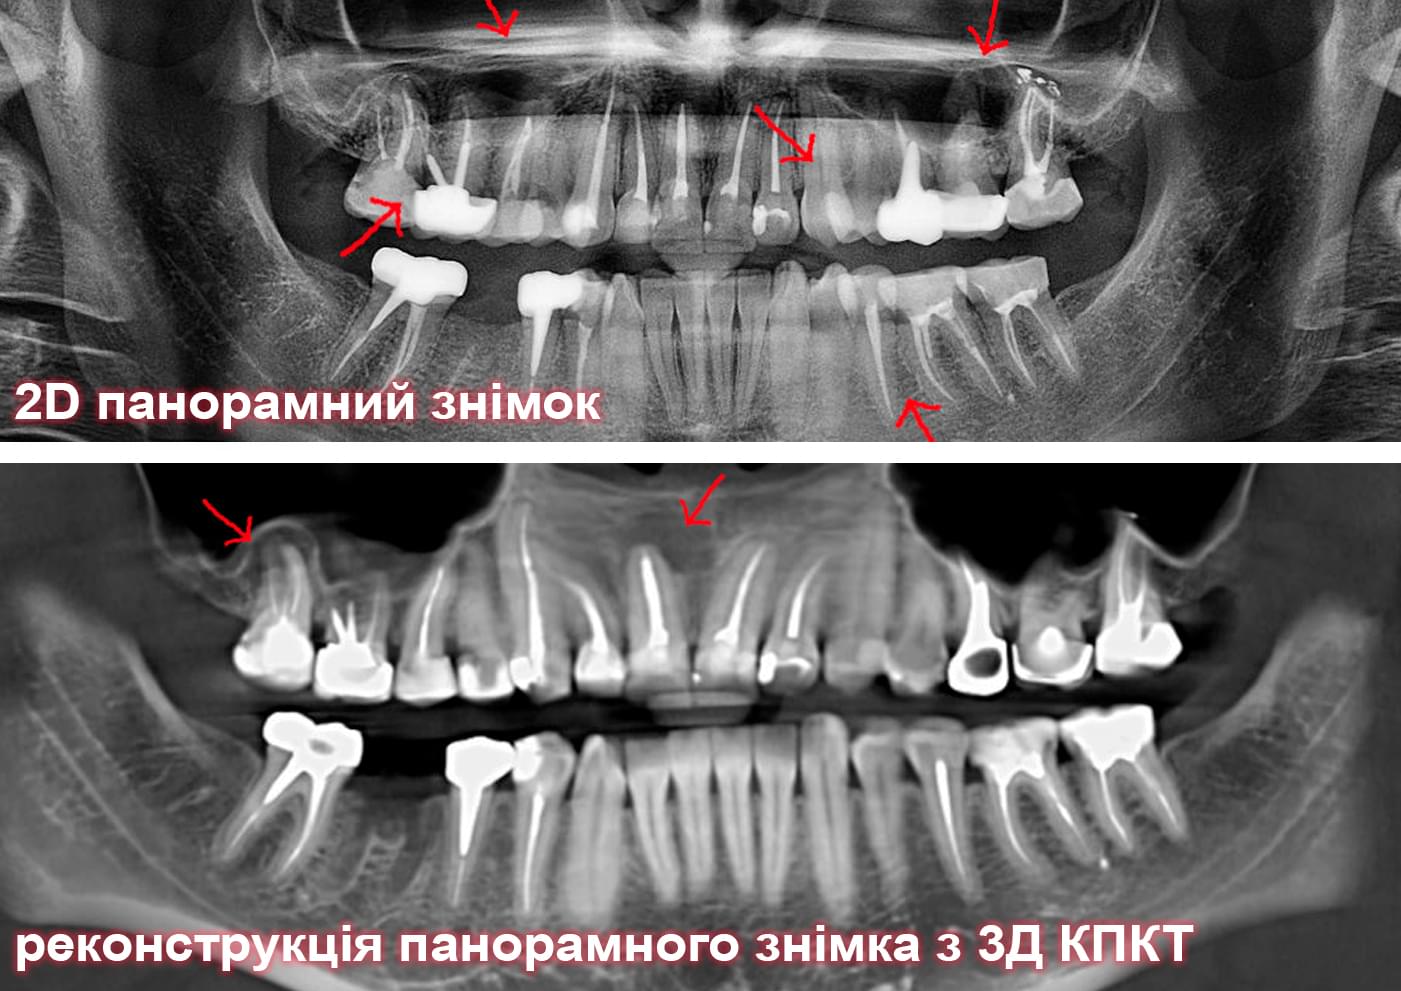

Головний недолік 2D-рентгену — це площинне зображення. Зуби, корені, щільна кістка та гайморові пазухи накладаються один на одного, створюючи «візуальний шум».

Візуальне порівняння (Кейс одного пацієнта)

Коли коріння «ховає сюрпризи» - Корені зубів часто мають складну кривизну, гачкоподібні закручення або розгалуження, які на звичайному 2D-знімку накладаються один на одного, створюючи ілюзію прямого каналу. На плоскій картинці неможливо побачити реальний об'єм та напрямок вигину, що критично важливо при видаленні «зубів мудрості» або ендодонтичному лікуванні. КТ MyRay дає змогу лікарю заздалегідь побачити 3D-геометрію кожного кореня, оцінити його близькість до нижньощелепного нерва чи гайморової пазухи та підібрати правильну тактику роботи. Це мінімізує ризики поломки інструменту в каналі або травмування сусідніх структур, перетворюючи складну хірургію на прогнозовану процедуру.

Чи варто робити КТ, якщо «і так все видно»? Наш досвід показує: переліковування зуба через неточну діагностику завжди коштує дорожче, ніж вчасне 3D-обстеження.